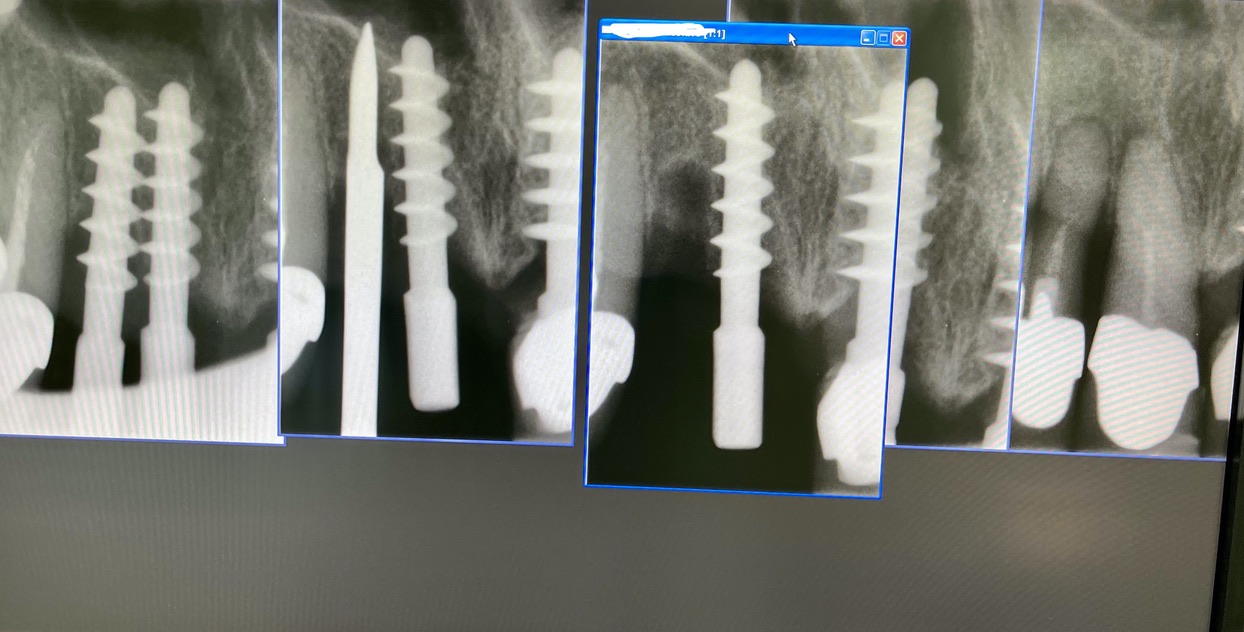

N° impianti esistenti 10

Data e n°interventi fatti: 2014:35 44 45 46. 2016: 16. 2017:22 23 24 25. 2019: 21

Tipo di impianto Tramonte

N° impianti inseriti : 2

Zona dentale: 11 12

App. Rx endorale : vix win Guidizzxolo